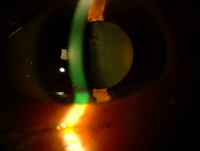

Mujer de 72 años con antecedentes personales de Diabetes Mellitus tipo 2, retinopatía diabética no proliferativa moderada en seguimiento por nuestro servicio e hipertensión arterial. Acude a urgencias por cuadro de dispepsia y melenas. Se practica endoscopia digestiva alta con hemostasia y toma de muestra, apreciándose úlcera gástrica prepilórica que es informada por Anatomía Patológica de “mucosa gástrica con signos inflamatorios crónicos y discreta cantidad de bacilos tipo H. Pylori” tras la realización de técnicas específicas de histoquímica (Figura 4).

Figura 4. Técnica histoquímica Warthin- Starry para detectar Helicobacter Pylori: se aprecia tinción de microorganismos tipo Helicobacter pylori en las luces glandulares.